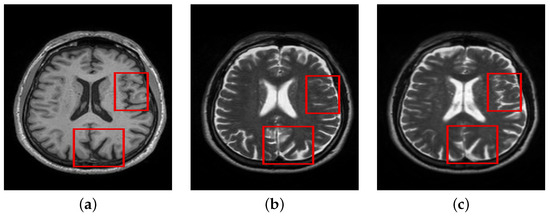

In this case, registration was performed between T1 and T2 volumes. Registration was done using 3D Slicer. Rigid Registration with 12 degrees of freedom was applied in all cases where T1 volume was fixed, while T2 was moved with reference to T1 in the registration process. The effect of registration can be better comprehended by visually inspecting the registered and unregistered T2 images with reference to T1 in Figure 4. It can be noticed that T1 and unregistered T2 slices are structurally similar; however, careful insight points to structural mismatches at various regions in the image. After applying registration, the structural similarity in the registered T2 image can be seen in the highlighted areas. In the following experimental sections, we further analyze the impact of registration on denoising and structural preservation in the presence of cross-modal image T2. The loss function used in this case is MSE.

Figure 4. Comparison of registered and unregistered images. (a) T1. (b) T2-Unregist. (c) T2-Regist.